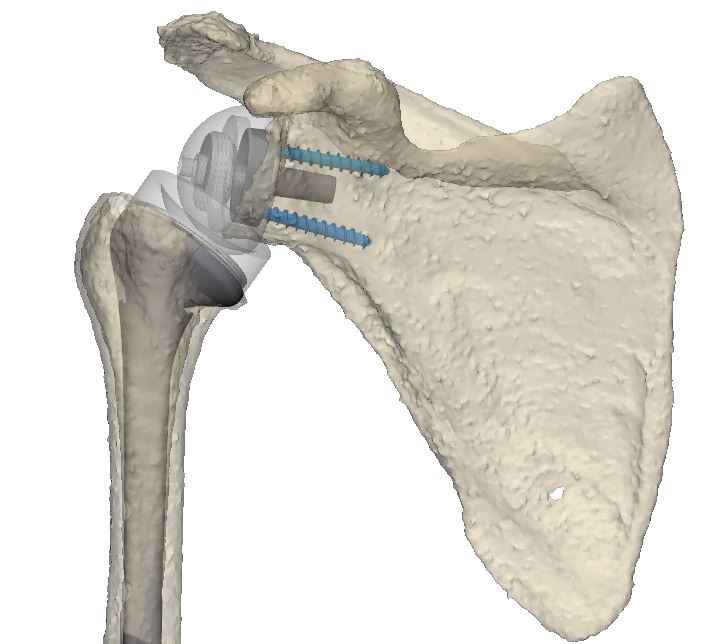

L’artroplàstia és una intervenció quirúrgica en la qual s’extreuen parts d’una articulació danyada i se substitueixen per una pròtesi de metall, plàstic o ceràmica d’una articulació sana. El 2019 es van realitzar més de tres milions de substitucions articulars a Europa i, a mesura que la població envelleix, es preveu que el nombre d’intervencions augmenti cada any. Tanmateix, la substitució articular és una operació complexa i un dels factors determinants més importants per a l’èxit és l’ajust de l’implant al cos i la seva adequació a característiques específiques de cada pacient com el sexe, l’alçada, el pes i l’edat.

Aquesta solució ha consistit en un conjunt d’eines i programes informàtics per al disseny, planificació i impressió 3D no aplicades fins ara a l’assistència sanitària, que funcionen de manera coordinada per agilitzar i millorar la qualitat dels processos quirúrgics. En concret, la solució incorpora: impressores 3D que amplien la capacitat productiva de l’I3PT i redueixen els temps en la fase de disseny; eines d’escaneig 3D per al mesurament de precisió preoperatòria de forma no invasiva que permeten l’avaluació de tot el cos per a optimitzar la biomecànica personalitzada, substituint així en algunes ocasions el TAC; i programari per a monitorar i realitzar un seguiment de principi a fi dels processos de fabricació i quirúrgics, garantint la qualitat necessària per a produir una pròtesi biomecànica personalitzada.

Planificació quirúrgica virtual per artroplàstia de maluc (foto superior) i espatlla (foto inferior)